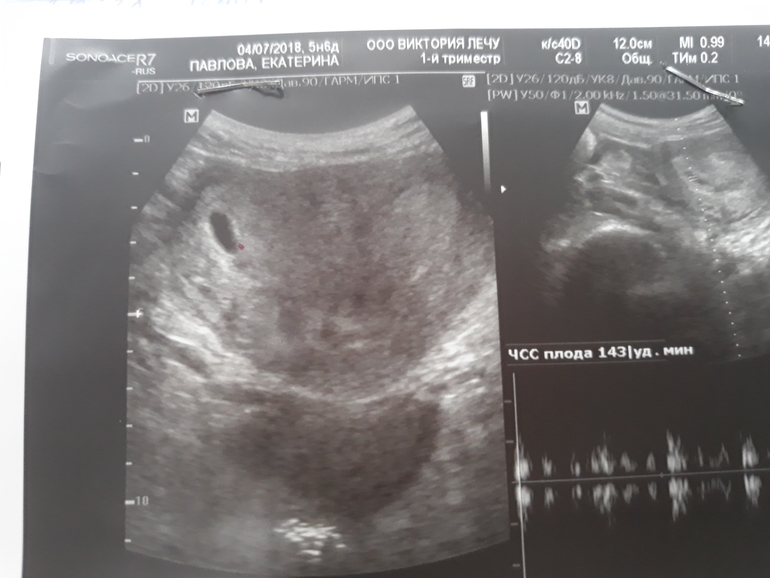

Вопросы про УЗИ, обследования и анализы: что, где, как, когда?Завтра будет ровно 6 недель. Ре сказала приходить к ней на следующей неделе слушать сердечко, но, как говорит мой муж, торопыжка я. Пошла на узи сегодня в инвитро. Врач дала послушать сердечко, много чего намерила, хотя я по картинкам малыша не увидела, но врач намерила ктр 3 мм. Теперь буду ждать следующей недели и пойду к ре на узи.

Здорово! Растите😊 У меня тоже сегодня 5недель и 6 дней и точно такие же размеры. Мне репродуктолог показала пульсирующий белый шарик и сказала что это малыш.